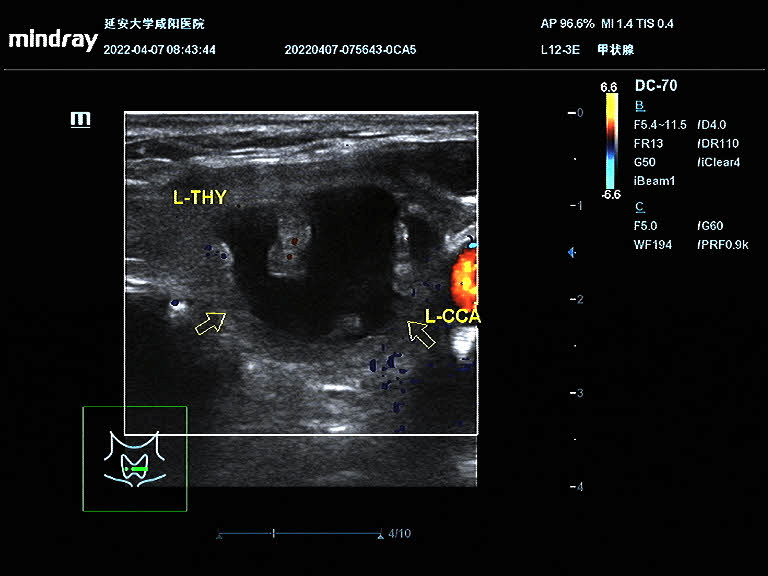

術(shù)前結(jié)節(jié)大小:44.9mm×31.8mm×22.2mm

王女士在半年前因頸部包塊就診于我院,超聲提示甲狀腺左葉囊實(shí)性包塊,因疫情原因未進(jìn)一步治療;近半年來(lái)包塊明顯增大,頸部膨隆,為進(jìn)一步治療就診于我院血液內(nèi)分泌科。彩超診斷為甲狀腺左側(cè)葉囊實(shí)性結(jié)節(jié),患者因懼怕疼痛,不愿手術(shù),選擇保守治療;后得知甲狀腺結(jié)節(jié)可以超聲引導(dǎo)下微創(chuàng)治療,遂聯(lián)系超聲科進(jìn)行咨詢;超聲科醫(yī)生對(duì)王女士的甲狀腺結(jié)節(jié)進(jìn)行評(píng)估后,就射頻消融術(shù)的優(yōu)點(diǎn)、術(shù)前的準(zhǔn)備、術(shù)中的風(fēng)險(xiǎn)、術(shù)后的注意事項(xiàng)詳細(xì)講解,王女士當(dāng)即決定選擇射頻消融術(shù)治療甲狀腺結(jié)節(jié)。4月9日下午在介入超聲手術(shù)室順利完成手術(shù),術(shù)后頸部?jī)H一個(gè)針眼大小。術(shù)中囊性部分抽吸為黑紅色粘稠液,實(shí)性部分消融治療,術(shù)后即刻造影結(jié)節(jié)內(nèi)未見(jiàn)造影劑回聲。